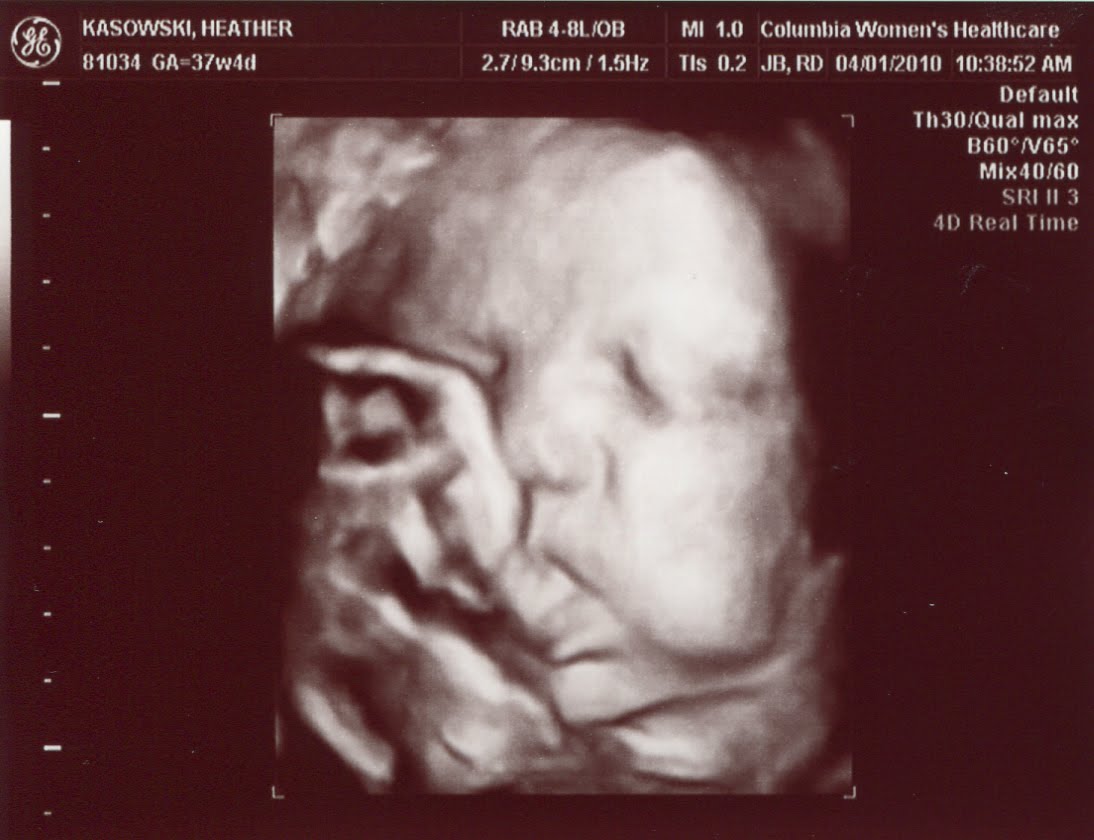

On Thursday, April 1 we had our scheduled ultrasound of the week. It was the last time we'd ever "see" Maelee alive. We had 3D ultrasounds, thankfully. She was sucking her thumb for us! And we got to see that she had quite a bit of hair which shocked us as we sort of assumed she'd be bald. Her little nose looked pretty big but we were told that is because they are usually smooshed. We didn't care what she looked like or who she looked like, we just wanted to see her. Once we hit April, we felt she could arrive any time as we figured she'd be big enough to be healthy and we were just so excited to meet her.